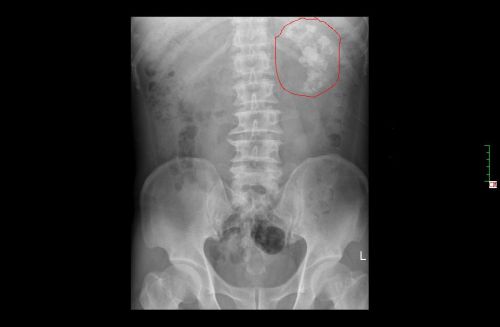

肾盂腔内长满铸型结石。

日前,娄底双峰县47岁的朱先生,因腰痛、血尿来到捷克论坛

泌尿外科二病室袁武雄教授处就诊,诊断为“肾铸型结石”,感染严重,且肾脏重度积水,单侧肾功能在40%以下。袁武雄教授精密分析患者各项指标后,为他制定了最适合的治疗方案,采用建立多个经皮通道、分两期的微创手术方式进行治疗。虽然短期内经历两次手术,但朱先生恢复很快,已经顺利出院。